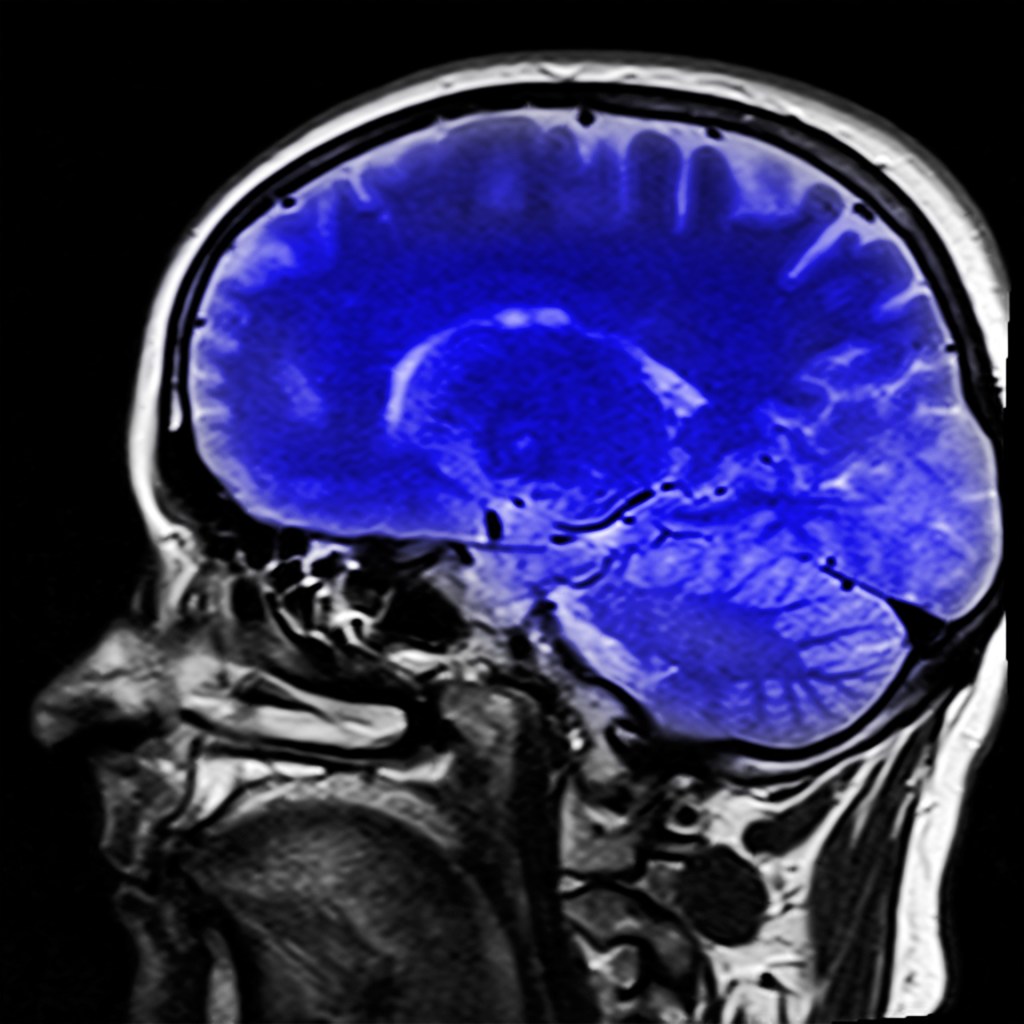

Brain — X-Ray

They are misunderstood because they still are. But don’t confuse misunderstanding with ignorance. We do not have all the answers regarding psychological behaviour and neurological potency. The brain is the most complex organ we possess, and people like narcopaths make it even more intricate.

They lack the brain chemistry to feel emotions the way regular people can. They are even limited in emotions; some are and never will be experienced. It is sad but doesn’t make them less dangerous or malignant. Nobody can save them. Do not try because you will fail. The attempt would be futile and with catastrophic results.